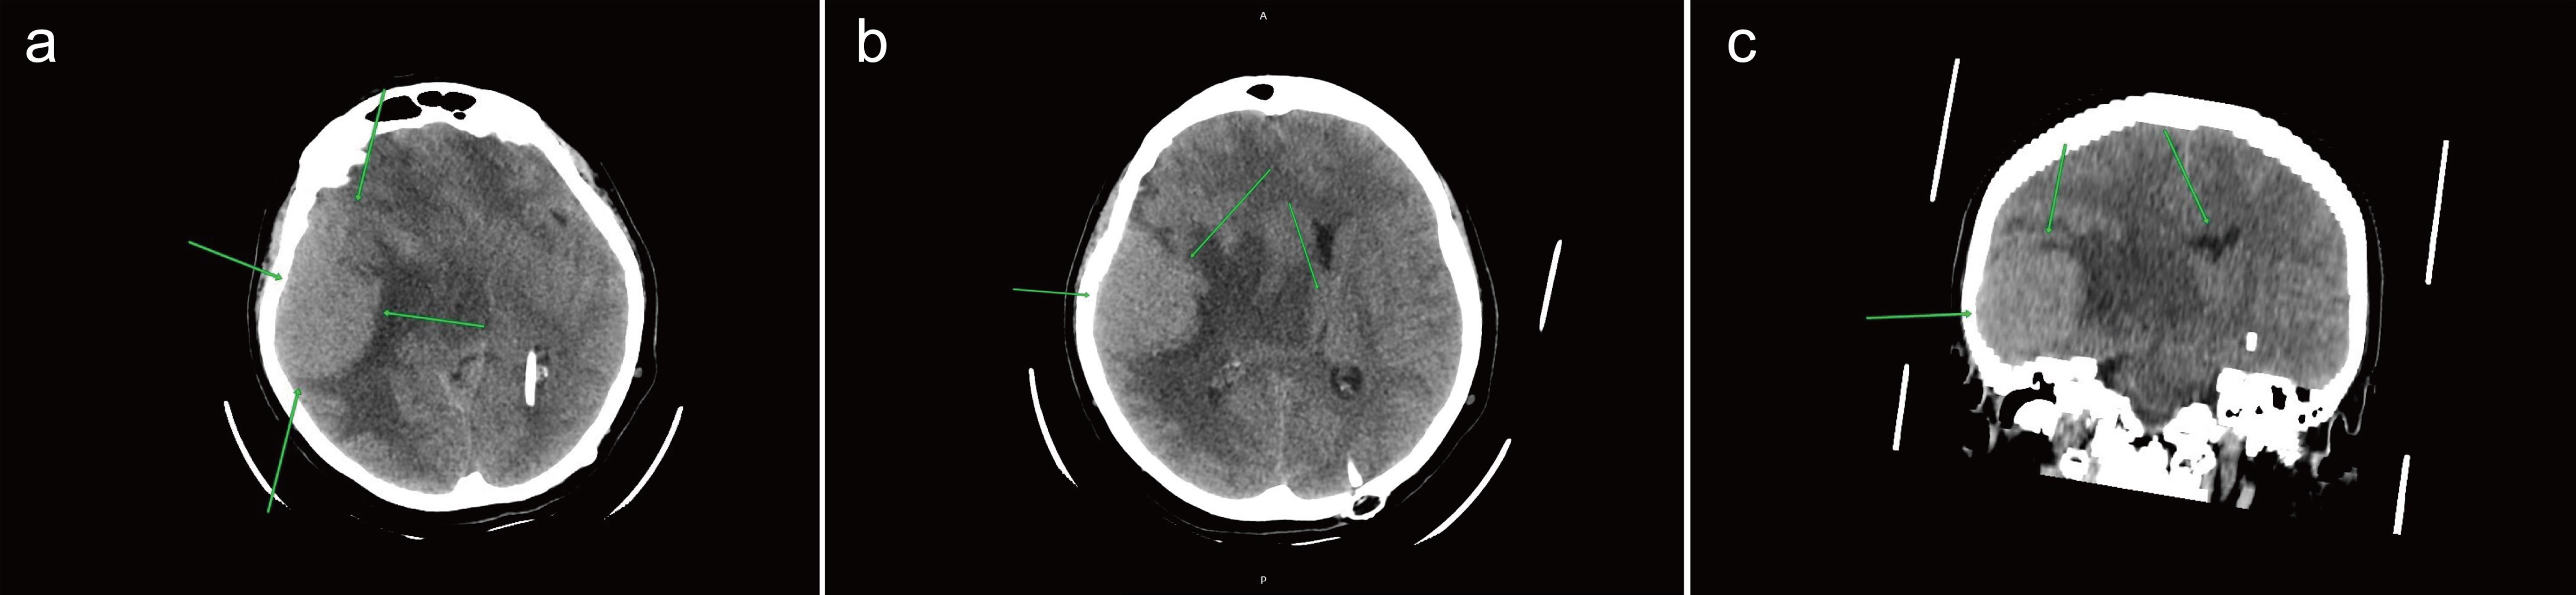

Fig. 2  Postoperative state after decompressive craniectomy in the right temporal region and removal of a space-occupying lesion in the right temporal lobe parenchyma (a) (February 6, 2022).

Displacement of midline structures to the left (b), compression (c), and deformation (d) of the ventricular system are observed (e).